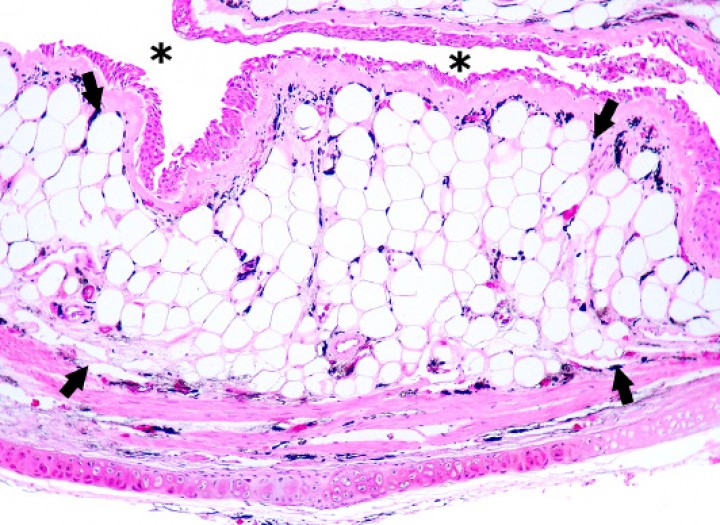

<p>Sapillo balear (<em>Alytes muletensis</em>). Se observa un colelito (cabezas de flecha) rodeado por secreción biliar condensada en la luz de la vesícula biliar (vb), la cual está distendida. El tejido adiposo (a) es marcadamente excesivo. slsc: seno linfático subcutáneo, h: hígado. Hematoxilina-eosina, x48.</p>

Figura 16

Sapillo balear (Alytes muletensis). Se observa un colelito (cabezas de flecha) rodeado por secreción biliar condensada en la luz de la vesícula biliar (vb), la cual está distendida. El tejido adiposo (a) es marcadamente excesivo. slsc: seno linfático subcutáneo, h: hígado. Hematoxilina-eosina, x48.

Se diagnosticó colelitiasis en la vesícula biliar de 4 sapillos baleares (Alytes muletensis) (4/131; 3,1%), con cálculos de hasta unos 6 mm de diámetro y sin evidencias de enfermedad obstructiva de vías biliares con excepción de un paciente. En este, la colelitiasis se acompañó de distensión prominente de la cavidad celómica (Fig. 15) debida a dilatación marcada de la vesícula biliar (Fig. 16) y de los conductos biliares intrahepáticos, con ruptura de la vesícula biliar y embolismo de bilis en el seno linfático subcutáneo, así como colangiohepatitis bacteriana ascendente de vías biliares secundaria a la presumible enfermedad biliar obstructiva. La bilis embolizada en el seno linfático, que contenía abundantes bacterias, causó engrosamiento de los tejidos blandos de la extremidad posterior izquierda (Fig. 15), donde se acompañó de necrosis muscular y cutánea (Fig. 17).

Un hallazgo relevante de este estudio para los programas de cría en cautividad del sapillo balear (Alytes muletensis) consiste en la presentación de 4 casos de colelitiasis; es posible que el pequeño tamaño de estos pacientes haya dificultado la detección de más casos, ya que las secciones seriadas de todo el cuerpo realizadas en los cadáveres pudieron dejar fuera del plano de corte colelitos pequeños o incluso a la misma vesícula biliar, en la cual se localizaron los colelitos en los sapillos baleares (Alytes muletensis) afectados. En uno de estos sapillos baleares (Alytes muletensis), esta enfermedad fue considerada la causa de la muerte, ya que cursó con evidencias de obstrucción y ruptura de vías biliares complicadas con colangiohepatitis bacteriana y embolismo de bilis hacia el seno linfático subcutáneo, que causó necrosis muscular y cutánea en la zona afectada. La etiopatogenia de la colelitiasis en estos sapillos baleares (Alytes muletensis) se desconoce, pero este último mostraba excesivo tejido adiposo y será necesaria una evaluación de la dieta ingerida por estos anfibios en colonias afectadas por tratarse de una fuente potencial de factores de riesgo de colelitiasis. Por ejemplo, la obesidad (o índices de masa corporal aumentados) e hipercolesterolemia/hipertrigliceridemia constituyen factores de riesgo de colelitiasis en pacientes humanos y en otras especies como la canina,[ Ali S, Ahamad ST, Talpur AS, Parajuli S, Farooq J. Prevalence of non-insulin-dependent diabetes mellitus among patients with cholelithiasis: a single-centered, cross-sectional study. Cureus 2018; 10(4):e2444. [PubMed] , Frybova B, Drabek J, Lochmannova J, et al. Cholelithiasis and choledocholithiasis in children; risk factors for development. PLoS One 2018; 13(5):e0196475. [PubMed] , Lee S, Kweon OK, Kim WH. Associations between serum leptin levels, hyperlipidemia, and cholelithiasis in dogs. PLoS One 2017; 12(10):e0187315. [PubMed] , Kim SB, Kim KH, Kim TN, et al. Sex differences in prevalence and risk factors of asymptomatic cholelithiasis in Korean health screening examinee: A retrospective analysis of a multicenter study. Medicine (Baltimore) 2017; 96(13):e6477. [PubMed] ] aunque la edad,[ Kim SB, Kim KH, Kim TN, et al. Sex differences in prevalence and risk factors of asymptomatic cholelithiasis in Korean health screening examinee: A retrospective analysis of a multicenter study. Medicine (Baltimore) 2017; 96(13):e6477. [PubMed] ] los factores genéticos (sobre todo genes codificadores de transportadores intestinal y hepático de colesterol),[ Rebholz C, Krawczyk M, Lammert F. Genetics of gallstone disease. Eur J Clin Invest 2018; 48(7):e12935. [PubMed] ] ciertos fármacos como la ceftriaxona[ Tuna Kirsaclioglu C, Çuhacı Çakır B, Bayram G, et al. Risk factors, complications and outcome of cholelithiasis in children: A retrospective, single-centre review. J Paediatr Child Health 2016; 52(10):944-949. [PubMed] ] y enfermedades subyacentes (como diabetes, hepatopatías o anemia hemolítica)[ Ali S, Ahamad ST, Talpur AS, Parajuli S, Farooq J. Prevalence of non-insulin-dependent diabetes mellitus among patients with cholelithiasis: a single-centered, cross-sectional study. Cureus 2018; 10(4):e2444. [PubMed] , Kim SB, Kim KH, Kim TN, et al. Sex differences in prevalence and risk factors of asymptomatic cholelithiasis in Korean health screening examinee: A retrospective analysis of a multicenter study. Medicine (Baltimore) 2017; 96(13):e6477. [PubMed] , Tuna Kirsaclioglu C, Çuhacı Çakır B, Bayram G, et al. Risk factors, complications and outcome of cholelithiasis in children: A retrospective, single-centre review. J Paediatr Child Health 2016; 52(10):944-949. [PubMed] ] pueden estar involucrados también.